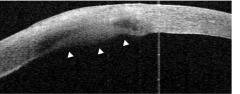

- 前节OCT:左眼角膜溃疡表面平整,后弹力层连续,内皮面见高反射均质内皮斑,与后弹力层界限清楚。

- 真菌性角膜炎出现内皮斑标志着真菌菌丝穿凿破坏后弹力层进入前房,因此前节OCT表现为后弹力层连续性中断,内皮斑形态不规则。

- 病毒性角膜炎出现内皮斑是因为炎性细胞在角膜后面大量聚集,是炎症反应重的标志,因此前节OCT表现为后弹力层连续完整,内皮斑均质且形态规则。